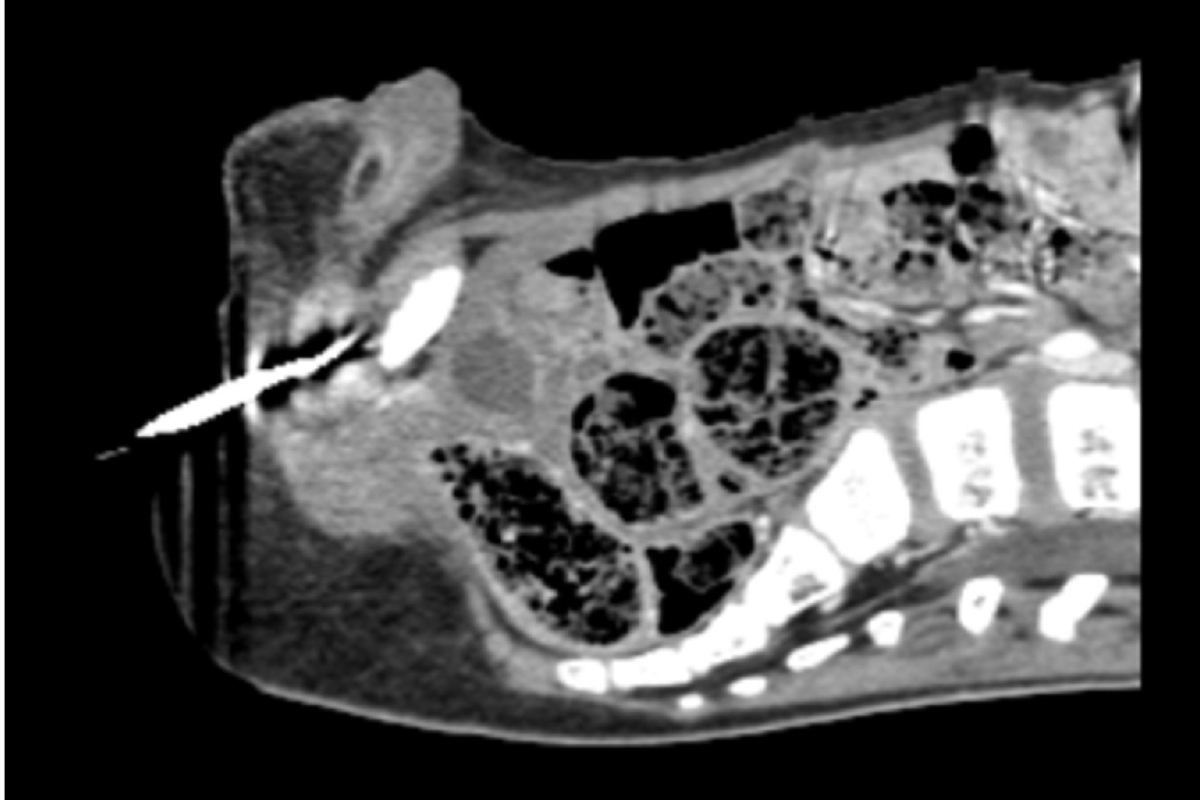

Menino senta em agulha de crochê e gancho torna cirurgia um desafio Ouvir 3 de janeiro de 2026 Um menino de 6 anos de Mekelle, na Etiópia, viveu uma emergência médica inusitada. Ele se sentou por acidente em uma agulha de crochê, com o objeto perfurando seu corpo na região do períneo. A retirada da agulha acabou se tornando um desafio maior do que o esperado devido ao formato em gancho do objeto. O caso foi relatado pelos médicos que atenderam a criança em um artigo publicado em pré-impressão na revista Urology Case Reports, em 30 de dezembro. “A escolha das técnicas de retirada dependia da localização anatômica da lesão e da profundidade da lesão causada pela agulha de crochê”, afirmam eles no texto. Leia também Distrito Federal Adolescente fura mão com agulha de crochê e é hospitalizado no DF Mundo Bebê fica com agulha esquecida na perna após erro de enfermeira Brasil Professor reutiliza agulha em aula e 44 alunos vão parar no hospital Brasil Goiás: Justiça absolve jovem que matou namorado com agulha de narguilé Gancho da agulha de crochê foi desafio As agulhas de crochê possuem uma ponta em formato de gancho para facilitar o trançado dos fios, mas isso impede a retirada simples do objeto quando ocorre algum acidente doméstico. O períneo, local que foi lesionado no acidente, também possui muitas terminações nervosas importantes, o que obrigou os médicos a cuidados especiais. Curiosamente, apesar da profundidade de entrada do objeto nº11, quando o menino chegou ao hospital após o acidente, não escorria sangue da ferida e nem tinha alteração urinária. Um raio X foi feito indicando a profundidade do objeto e os melhores meios de retirada durante a cirurgia. Exame de imagem mostra a profundidade da área atingida pela agulha Após uma anestesia local, a equipe retirou a agulha com uma incisão que permitiu cortar o metal do objeto para movimentá-lo levemente. O método possibilitou a retirada do objeto com pinças evitando danos maiores aos tecidos do menino. A criança recebeu alta dois dias após o procedimento e não teve outras complicações. “Até onde sabemos, este é o primeiro caso de uma lesão perineal penetrante causada por agulhas de crochê”, concluem os médicos. Notícias